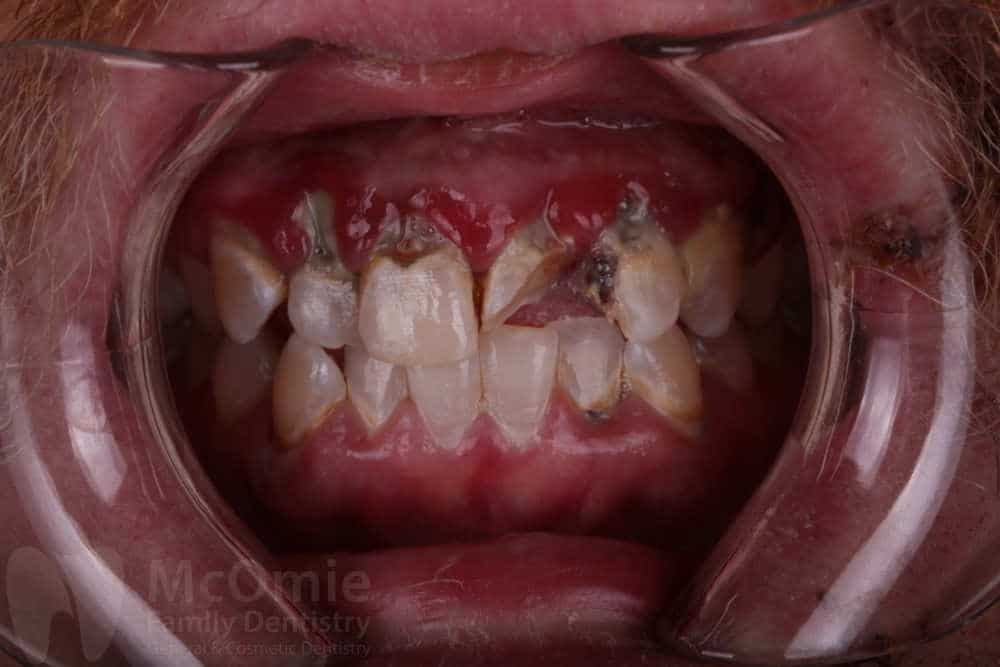

This patient came to us after a traumatic facial injury that left several front teeth fractured and caused severe damage to the surrounding gum tissue. Initial photos show broken teeth and torn soft tissue resulting from the accident. Treatment began with gum surgery and supportive therapy to stabilize and promote healing. Once the tissue improved, crowns were placed on the front four teeth to restore strength, appearance, and function. The result is a smile that looks natural and healthy, with both teeth and gums healing beautifully just two weeks post-op.